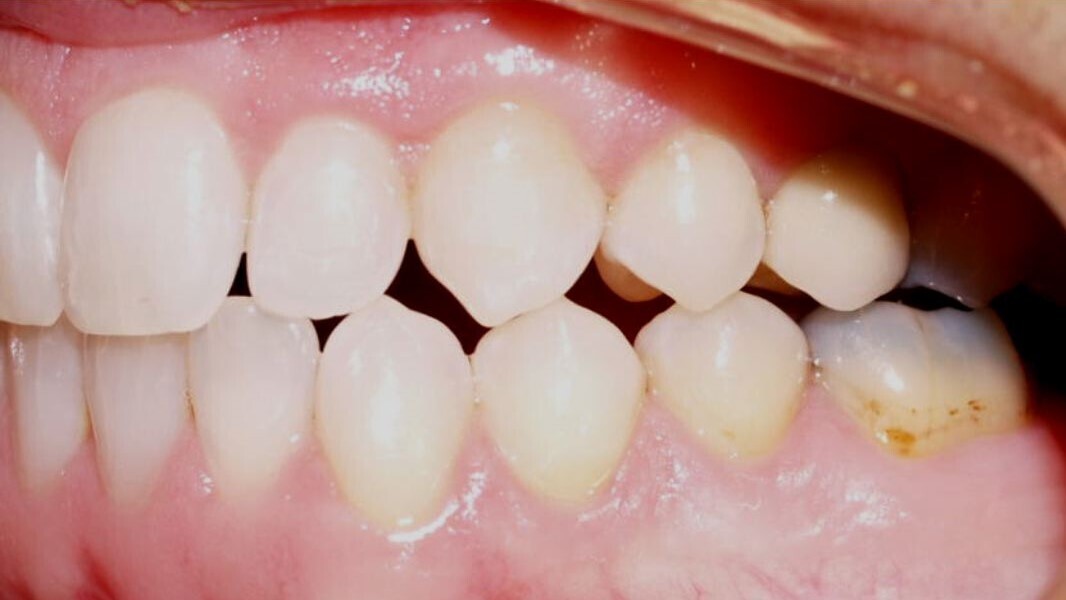

Severely rotated teeth

Aligners alone will fail because the plastic simply cannot adequately deliver the appropriate rotational couples—especially in cylindrical teeth. This is so despite ingenious attachment combinations that will indeed achieve some rotation, but not much. Instead use bonded buttons and elastomerics strategically placed into precision cut-outs of the first round of aligners and activated to produce force couples that will indeed rotate teeth (Figs. 1–3). The outcome is much more assured rotations in a shorter amount of time and with less chance of loss of aligner tracking.

Fig. 1: Severely rotated mandibular left second premolar.